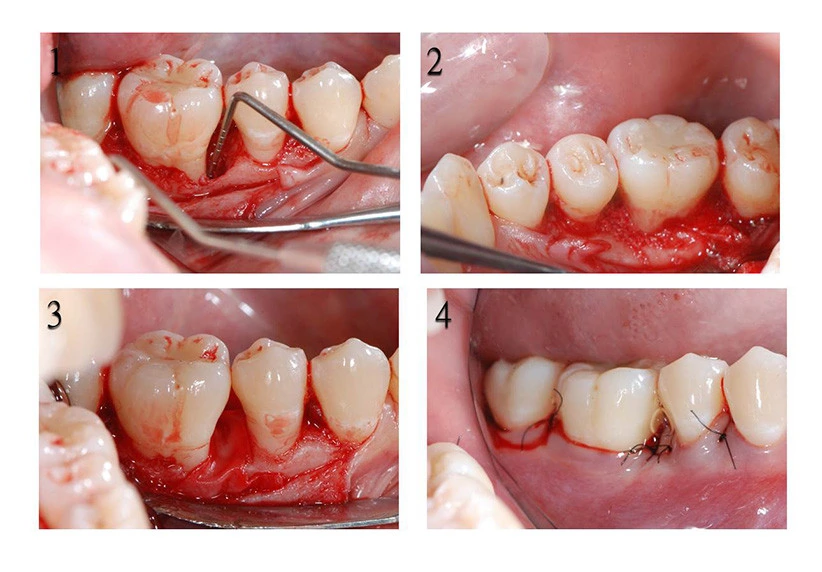

牙周再生手術